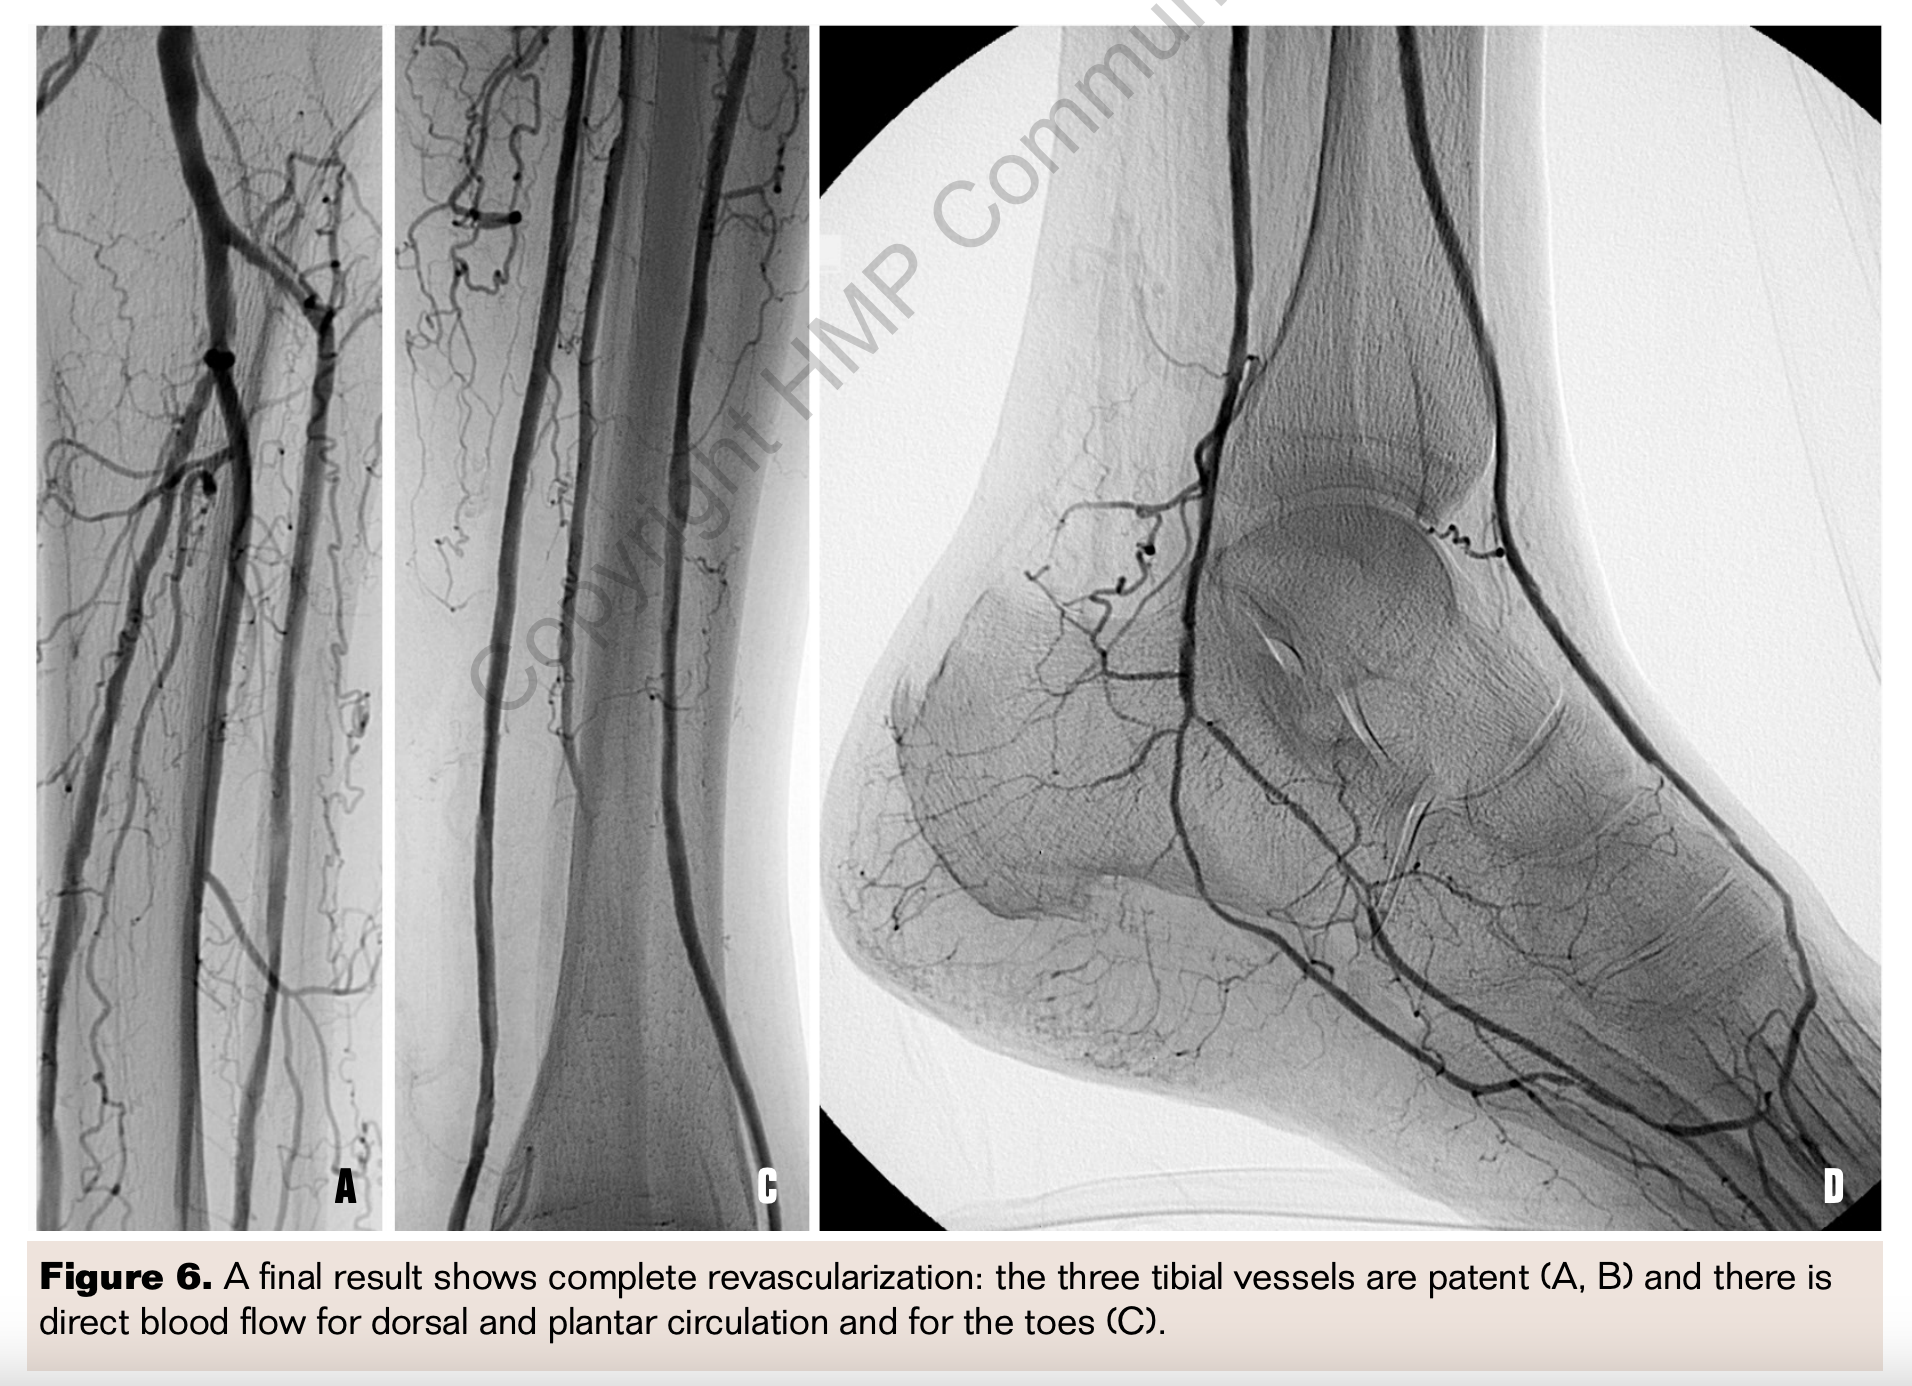

In addition to the transcollateral approaches described, there are other collateral pathways or natural anastomoses between pedal arteries that allow performing retrograde-antegrade recanalization of the pedal and tibial vessels, and they represent an alternative option to recanalize the target pedal vessel (Figures 5 and 6).